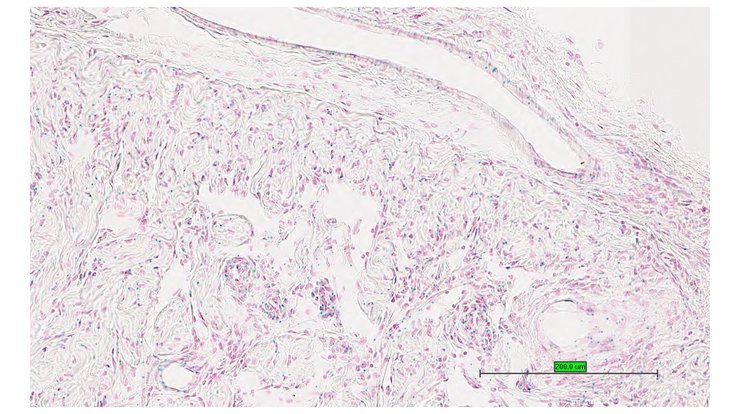

Structure Level Pattern Image Note

TS28: trigeminal nerve Present UC Davis_1878620

Specimen UC Davis_1878663: postnatal adult; Apbb2tm1.1(KOMP)Vlcg/Apbb2+ (more )

TS28: trigeminal nerve Absent UC Davis_1878663